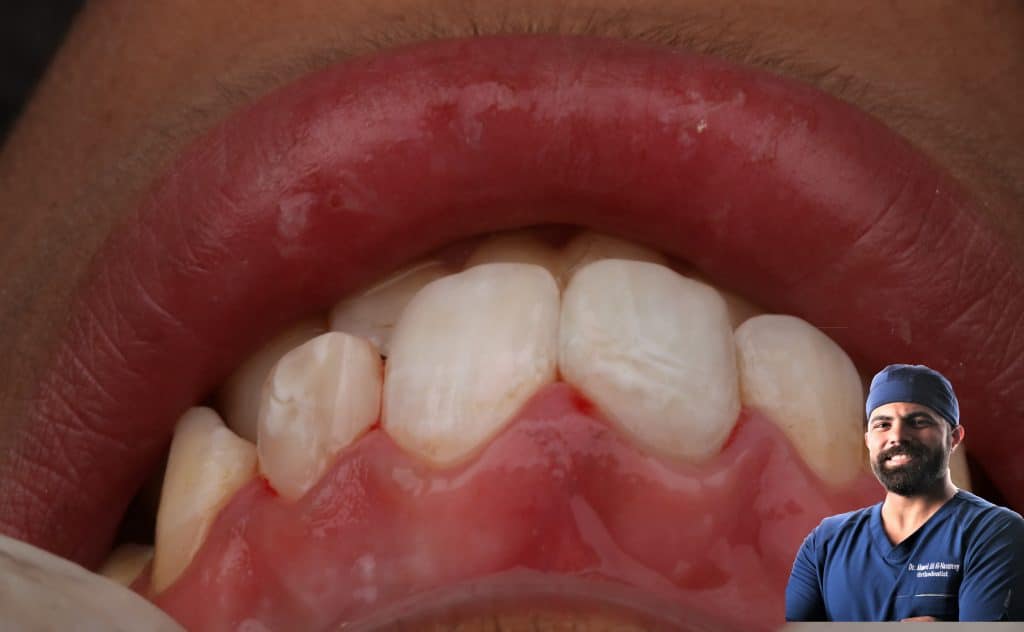

✅internal bleaching with WBT as described by p.mange

✅composite restoration

Internal bleaching by using hydrogen peroxide by WBT

describe by p.mange